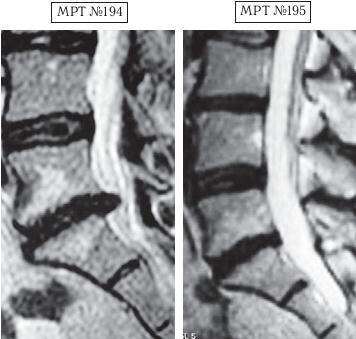

Пример № 2.

На МРТ № 194 наблюдается состояние поясничного отдела позвоночника после трёх операций: рецидив — грыжа межпозвонкового диска в сегменте LV-SI стеноз спинномозгового канала.

На МРТ № 195 — состояние поясничного отдела позвоночника после лечения методом вертеброревитологии.